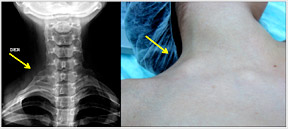

Departamento de Cirugía Vascular estudia extraño Sindrome de Opérculo Torácico Arterial siendo uno de los pocos equipos que aporta en esta materia en el mundo